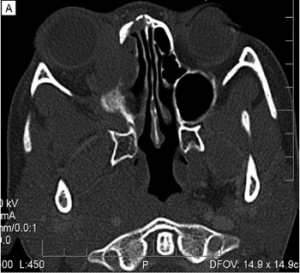

Imaging can aid in diagnosis, especially in cases of orbital soft tissue or EOM involvement, which are better appreciated on orbital imaging. Imaging techniques include CT or MRI of the orbits, and fluorodeoxyglucose (FDG)-PET/CT scan. MRI will demonstrate isointensity on T1-weighted lesions, hypointensity on T2-weighted lesions, and homogenous gadolinium enhancing lesions.[42] FDG-PET scan can be used for systemic evaluation in IgG4-RD, as it can locate distant and/or clinically silent lesions.[43] There are currently no guidelines on how often FDG-PET/CT should be performed.